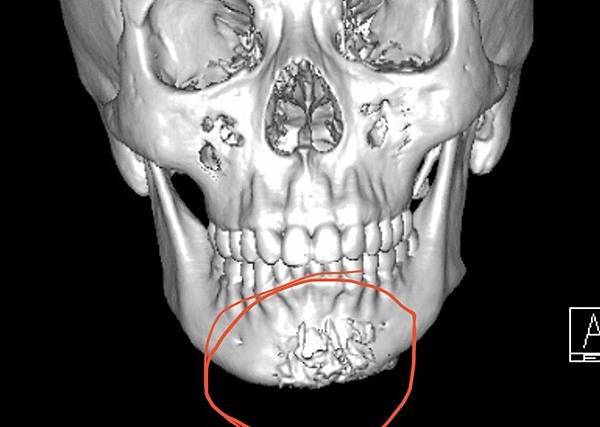

成型的下巴植體手術常遇到的就是不吻合臉型, 甚至可能因此歪斜(下圖),因此客製化假體相當重要避免術後不吻合或嘴邊斷層的嘎尬。

下圖重修歪斜下巴的過程:

李醫師針對重修下巴(上圖)的求美者有堅持:

1.務必3D電腦斷層評估與設計

2.配合工程師計算出落差數據

3.患者本人與照片分析評估及溝通